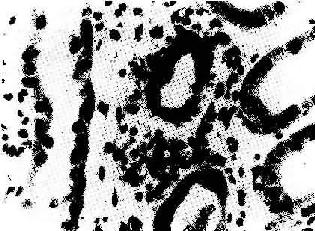

二、排斥反应的病变移植排斥反应按形态变化及发病机制的不同有超急性排斥反应、急性排斥反应和慢性排斥反应三类。兹以肾移植中各类排斥反应的病理变化为例加以说明。类似的变化亦可见于其他组织、器官的移植。 1.超急性排斥反应 是受体对移植物的一种迅速而剧烈的反应,一般于移植后数分钟至24小时内出现.本型反应的发生与受体血循环中已先有供体特异性HLA抗体存在,或受体、供体ABO血型不符有关.这主要是由于循环抗体与移植物细胞表面HLA抗原相结合并激活补本系统,释放出多种生物活性物质,从而引起局部炎症、血管内皮细胞损害、血栓形成和组织损伤。本质上属Ⅱ型变态反应,但广泛分布的急性小动脉炎、血栓形成和因而引起的组织缺血性坏死,在形态上类似于Arthus反应。 移植肾肉眼观表现为色泽迅速由粉红色转变为暗红色,伴出血或梗死,出现花班状外观。体积明显肿大,质地柔软,无泌尿功能。镜下表现为广泛的急性小动脉炎伴血栓形成及缺血性坏死。受累的动脉壁有纤维素样坏死和中性粒细胞浸润,并有IgG、IgM、补体沉积;管腔中有纤维蛋白和细胞碎屑阻塞。肾小球肿大,肾小管上皮细胞发生缺血性坏死,间质水肿并有中性粒细胞浸润,有时还可有淋巴细胞和巨噬细胞浸润。 2.急性排斥反应 较常见,在未经治疗者此反应可发生在移植后数天之内;而经过免疫抑制治疗者,可在数月或数年后突然发生。此种排斥反应可以细胞免疫为主,也可以体液免疫为主,有时两者可同时参与作用。 (1)细胞型排斥反应:常发生在移植后几个月,临床上表现为骤然发生的移植肾功能衰竭。镜下可见肾间质明显水肿伴有大量细胞浸润,以单核细胞和淋巴细胞为主,并夹杂一些具有嗜酸性胞浆和水泡状胞核的转化淋巴细胞和浆细胞。免疫组化染色证实有大量CD4+、CD8+细胞存在。肾小球及肾小管周围毛细血管中有大量单核细胞,间质中浸润的淋巴细胞可侵袭肾小管壁,引起局部肾小管坏死(图4-4)。

图4-4 肾移植急性排斥反应 肾间质水肿,肾小管上皮细胞变性,间质及毛细血管内有大量单核细胞 (2)血管型排斥反应:主要为抗体介导的排斥反应(CMC,ADCC和免疫复合物形成),往往在稍后出现,以突出的血管病变为特征。表现为肾细、小动脉的坏死性血管炎,可呈弥漫或局灶性分布。免疫荧光证实有免疫球蛋白、补体及纤维蛋白沉积,肾小球毛细血管袢亦可受累。纤维蛋白样坏死的血管壁内常有淋巴细胞、泡沫细胞及中性粒细胞浸润,腔内可有血小板凝集、血栓形成(图4-5)。后期的血管内膜纤维化,管腔狭窄。间质内常有不同程度淋巴细胞、巨噬细胞及浆细胞浸润。肉眼观,肾常明显肿大,呈暗红色并有出血点,有时可出现黄褐色的梗死灶,可伴有肾盂及肾盏出血(图4-6).临床上,移植肾出现功能减退,大剂量免疫抑制剂疗效不佳。